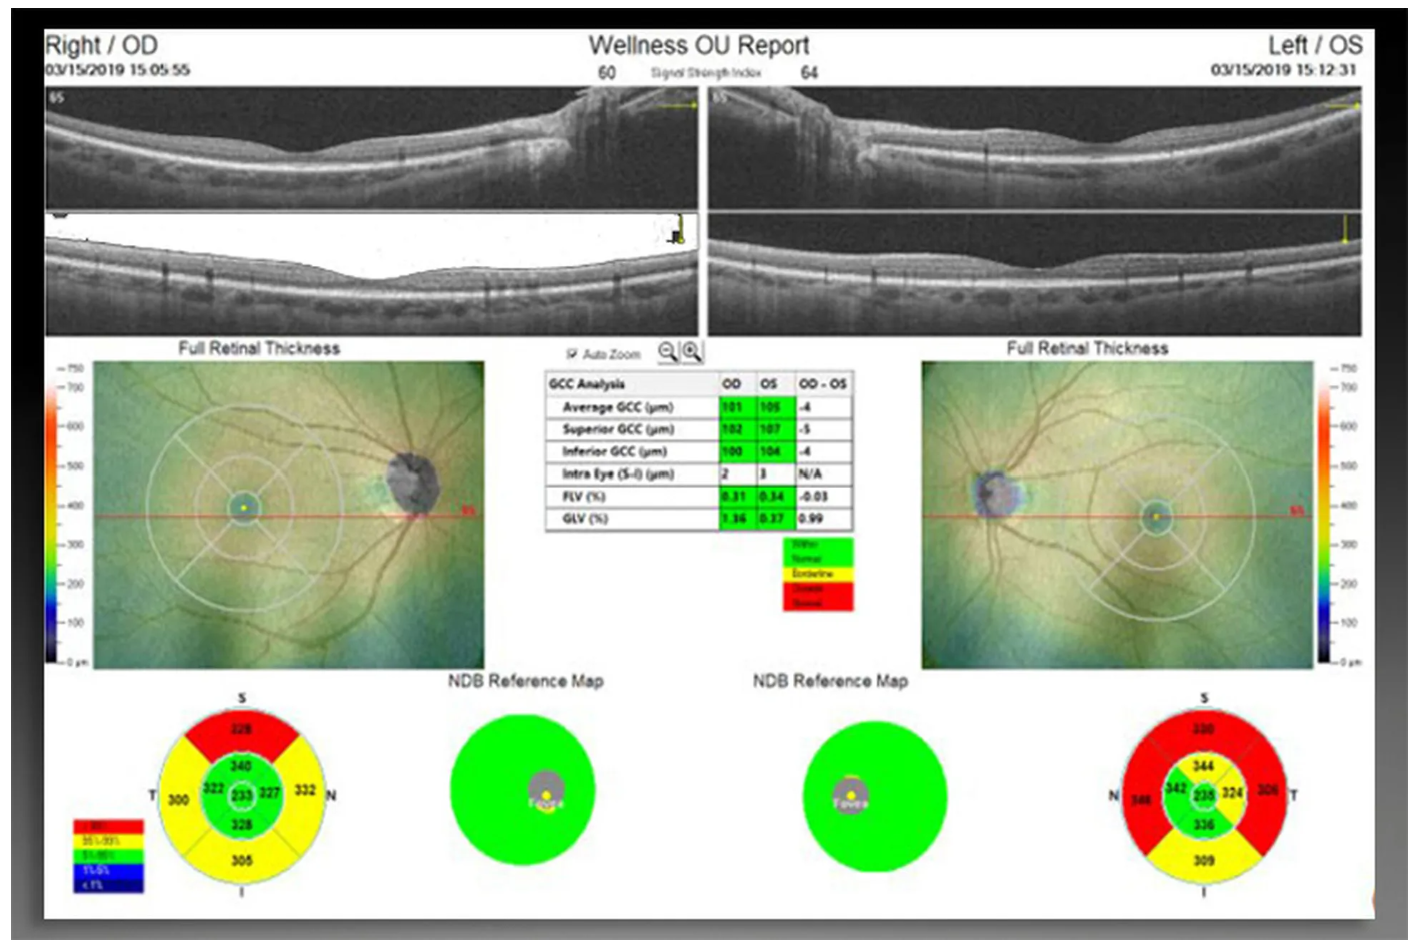

Оптический когерентный томограф Optovue Solix обладает повышенной скоростью сканирования — 120 000 А-сканов в секунду. SOLIX предоставляет множество инструментов для нового поколения борьбы с заболеваниями, которые повышают пропускную способность и обеспечивают превосходный уход за пациентами. В отличие от томографов более ранних поколений ОКТ SOLIX OPTOVUЕ может определять наличие конкрементов и новообразований сосудов сетчатки и хориоидеи, позволяет получать максимально точную послойную визуализацию структур глаза.

- Программа AngioAnaliticsTM для количественного анализа сосудов сетчатки;